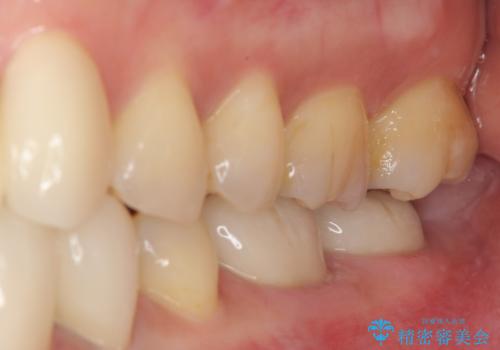

見た目、噛み合わせともに満足していただけました。